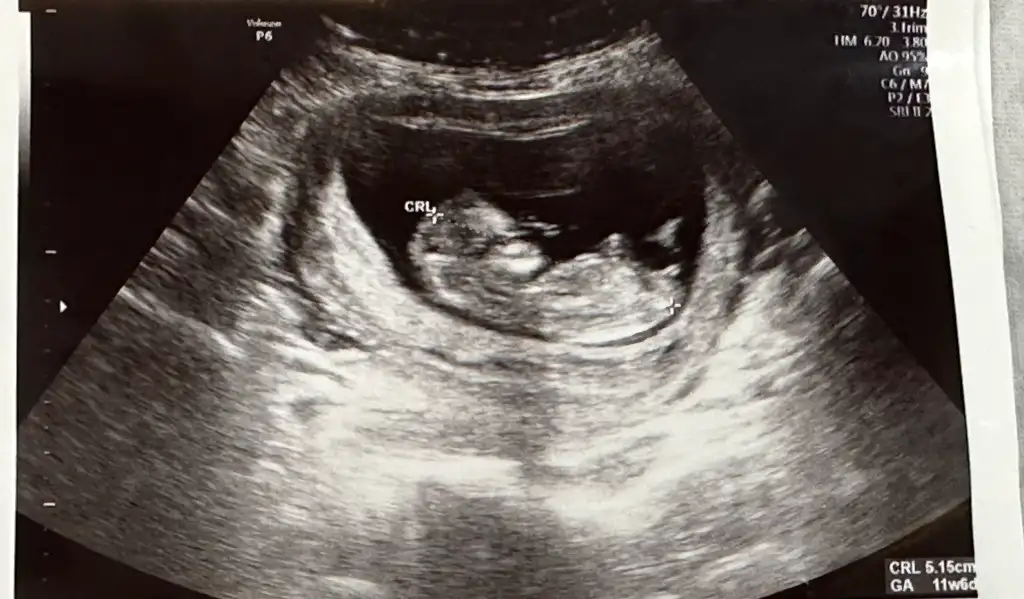

Merhaba öncelikle sağlıcakla kucağına almayı nasip etsin rabbim sizlere bağışlasın. Gebeliğin ileri haftalarda olduğu için birşey danışmak istiyorum başına geldimi geldiyse nasıl oldu diye ben gebeliğim 8+0 dayım 3 gün önce gece bir kere sadece açık kahve akıntım oldu adet olacakmisim gibi ağrı ateş ter basmalar vardı doktor bana bebek iyi kalp atışları da var iyi ama bı kanama alanın var progesteron verdi sabah akşam kullan dinlen dedi ve ayın 10 nda kontrole gideceğim sormak istediğim duzelirmi yada kalp atışlarında olumsuz birşey olur mu çok canım sıkıldı bu durumaSevgili anneler merhaba 12.05.2025 resimde

İyi günler. 17haftalık resmi sanki bizimkine benziyor. Bende belirsizlik halaSevgili anneler merhaba 12.05.2025 resimde

Doktor 17 haftaya girerken iki kez yüzde 80 kız dedi daha sonra 18+2 de gittim %99 erkek dedi bu şekilde olan değişen varmı 22 haftada detaylı ultrason giricem iyice muallakta kaldım